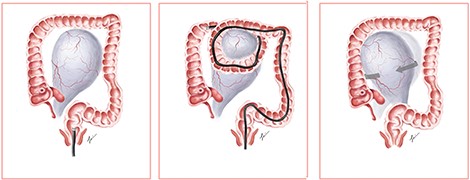

Looping of the endoscope is one of the most common challenges encountered during colonoscopy. A study by Shah et al. reported ~91% of looping during colonoscopy, with the ‘N-sigmoid’ loop being the most common [6]. Looping can result in the loss of control of the endoscope, patient discomfort and increase in rates of incomplete colonoscopy [7]. Various manoeuvres are employed to counteract looping, such as the application of abdominal compression [8].

We propose a postulated mechanism of ovarian torsion in this patient (Fig. 3). Due to the large size of the ovarian mass, looping during colonoscopy could have caught the ovarian mass between the bowels, leading to the twisting of the mass on its pedicle by the looped segment of the bowel. Application of abdominal compression to advance the endoscope could have precipitated further twisting of the mass, resulting in ovarian torsion. Although causality between colonoscopy and ovarian torsion cannot be proven, the development of acute abdominal pain shortly after colonoscopy prompts us to consider that the colonoscope could have mechanically twisted the ovary on its pedicle.